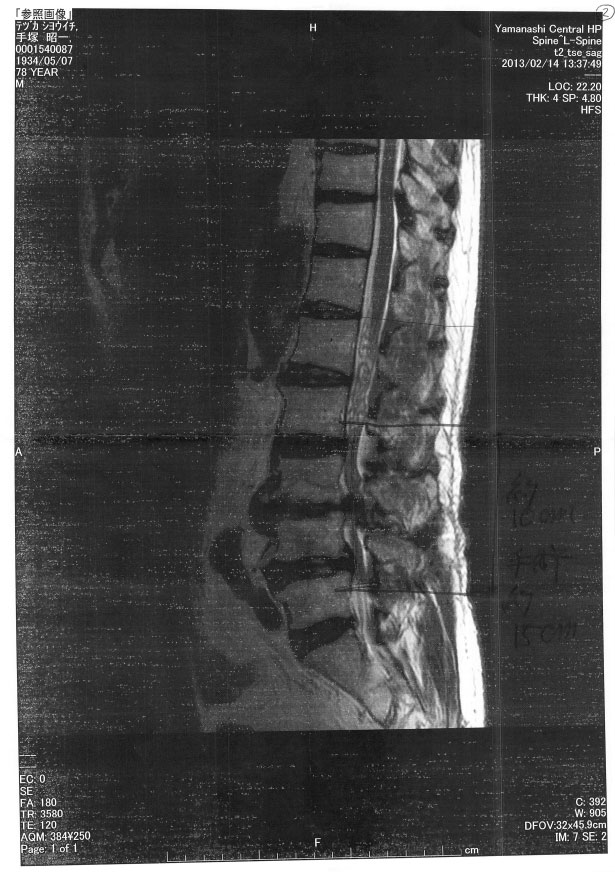

2013.2.14  13時30分よりY県立中央病院MRI検査を受ける。

検査後の診察で脊柱の2番から5番の間の3ケ処で、狭窄がおきておりその範囲は約10cmで、手術をする場合は約15cm切るとの事。

MRI検査の結果の画像はの通り。